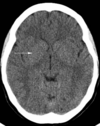

1

Q

A

quadrigeminal cistern